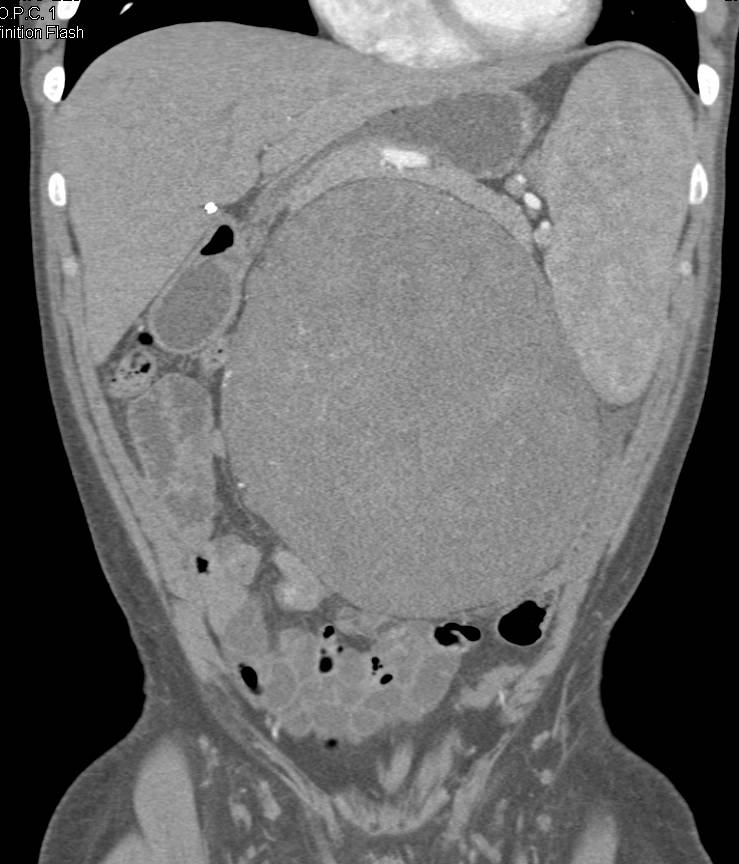

КТ ретроперитонеального фиброза: Изображения и диагностика

Раздел: Мудрость в деталях